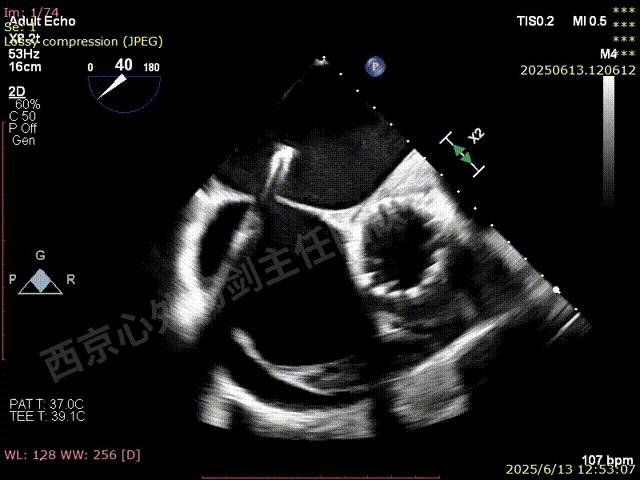

SGC撤回右房后,观察到有右向左的反流,血氧饱和度下降

行房间隔封堵

M-TEER术后三尖瓣反流减轻